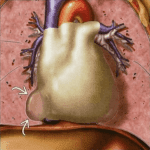

Nang Màng Tim | Bài giảng CĐHA

Nang màng tim (Pericardial cyst) hay nang màng phổi-màng ngoài tim là bệnh bẩm sinh, thường phát hiện tình cờ, ít gây triệu chứng. Đứng thứ 2 trong số u nang trung thất, chiếm 6%. Đa số nang được lát bằng một lớp tế bào trung mô, chứa đầy dịch trong.